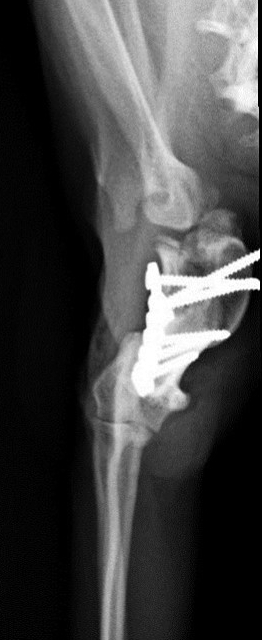

Die kleine verschmuste Maus ist so tapfer, inzwischen hat sie bereits beide OPs gut überstanden. Bei der ersten OP wurde die Biegung im Oberarm herausgeschnitten und der Oberarm in gestreckter Position mit einer Platte befestigt. Die Röntgenkontrolle hat gezeigt, dass der Knochen schon gut verheilt ist, Ariel kann damit sogar schon wieder ganz gut laufen. So konnte also auch schon die zweite OP stattfinden, bei der ihr luxiertes linkes Schultergelenk in eine normale Position gebracht und die Bänder gestrafft wurden.

...und schon fast verheilt!

Ihr linkes luxiertes Schultergelenk vor und nach der OP: